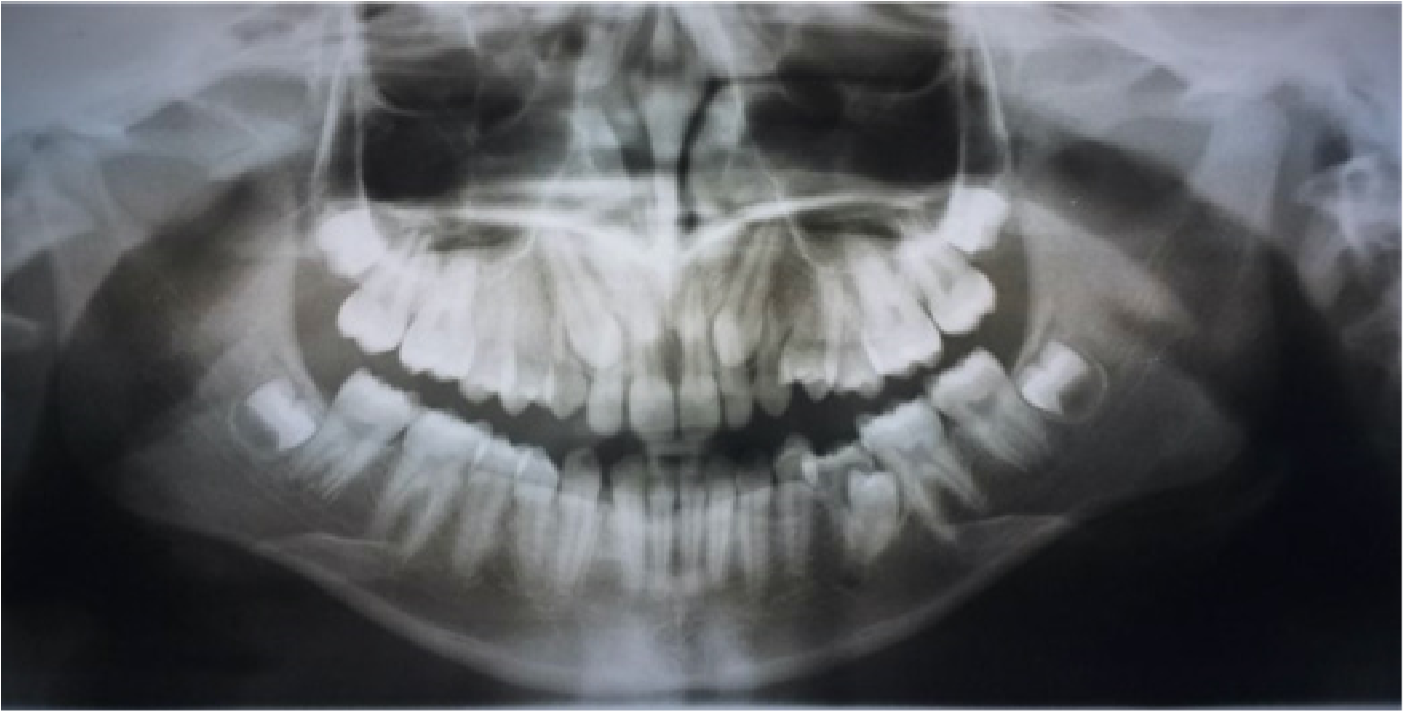

Caso 3. Paciente masculino de 15 años quien acude a consulta por falta de espacio en los maxilares. Los padres firmaron consentimiento informado. No refieren tratamiento de ortodoncia u ortopedia previo. Paciente con antecedentesdealergiaalosácaros,intervención quirúrgica de amígdalas y adenoides a los 7 años, con múltiples tratamientos por sinusitis. Alcanzó el desarrollo puberal a los 14 años y medio. Padre y madre tuvieron tratamiento de ortodoncia por apiñamientos y discrepancias estéticas. Al momento del examen diagnóstico presentó maloclusión Clase I con mordida profunda anterior, retención prolongada de los segundos molares inferiores primarios derecho e izquierdo debajo del plano oclusal inferior y debajo del plano oclusal inferior, con impactación de segundos premolares inferiores derecho e izquierdo. Además los incisivos laterales superiores se observan estrechos mesio-distalmente (Figura 3). El tratamiento consistió en: remoción del segundo molar primario inferior izquierdo y derecho retenido, terapia ortodóncica con aparatología fija .022 de Straightwire en ambos arcos dentarios.

Figura 3. Radiografía panorámica y periapicales iniciales, mostrando los segundos molares primarios retenidos en infraoclusión y la impactación de los segundos premolares inferiores.